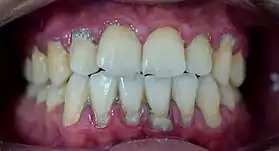

Calculus formation is associated with a number of clinical manifestations, including bad breath, receding gums and chronically inflamed gingiva. Brushing and flossing can remove plaque from which calculus forms; however, once formed, calculus is too hard (firmly attached) to be removed with a toothbrush. Calculus buildup can be removed with ultrasonic tools or dental hand instruments (such as a periodontal scaler).

Plaque accumulation causes the gingiva to become irritated and inflamed, and this is referred to as gingivitis. When the gingiva become so irritated that there is a loss of the connective tissue fibers that attach the gums to the teeth and bone that surrounds the tooth, this is known as periodontitis. Dental plaque is not the sole cause of periodontitis; however it is many times referred to as a primary aetiology. Plaque that remains in the oral cavity long enough will eventually calcify and become calculus.[15] Calculus is detrimental to gingival health because it serves as a trap for increased plaque formation and retention; thus, calculus, along with other factors that cause a localized build-up of plaque, is referred to as a secondary aetiology of periodontitis.

When plaque is supragingival, the bacterial content contains a great proportion of aerobic bacteria and yeast,[18] or those bacteria which utilize and can survive in an environment containing oxygen. Subgingival plaque contains a higher proportion of anaerobic bacteria, or those bacteria which cannot exist in an environment containing oxygen. Several anaerobic plaque bacteria, such as Porphyromonas gingivalis,[19] secrete antigenic proteins that trigger a strong inflammatory response in the periodontium, the specialized tissues that surround and support the teeth. Prolonged inflammation of the periodontium leads to bone loss and weakening of the gingival fibers that attach the teeth to the gums, two major hallmarks of periodontitis. Supragingival calculus formation is nearly ubiquitous in humans,[20][21][22] but to differing degrees. Almost all individuals with periodontitis exhibit considerable subgingival calculus deposits.[15] Dental plaque bacteria have been linked to cardiovascular disease[23] and mothers giving birth to pre-term low weight infants,[24] but there is no conclusive evidence yet that periodontitis is a significant risk factor for either of these two conditions.[25]